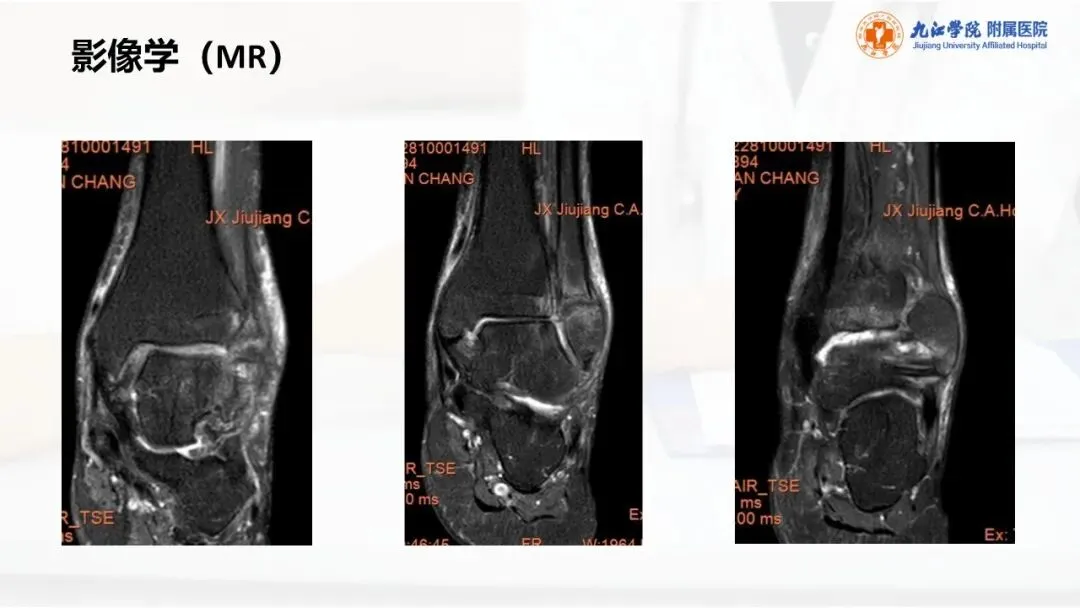

当前位置:首页>PPT>PPT纯享:陈旧性踝关节骨折的治疗案例(内附文献推荐)

PPT纯享:陈旧性踝关节骨折的治疗案例(内附文献推荐)